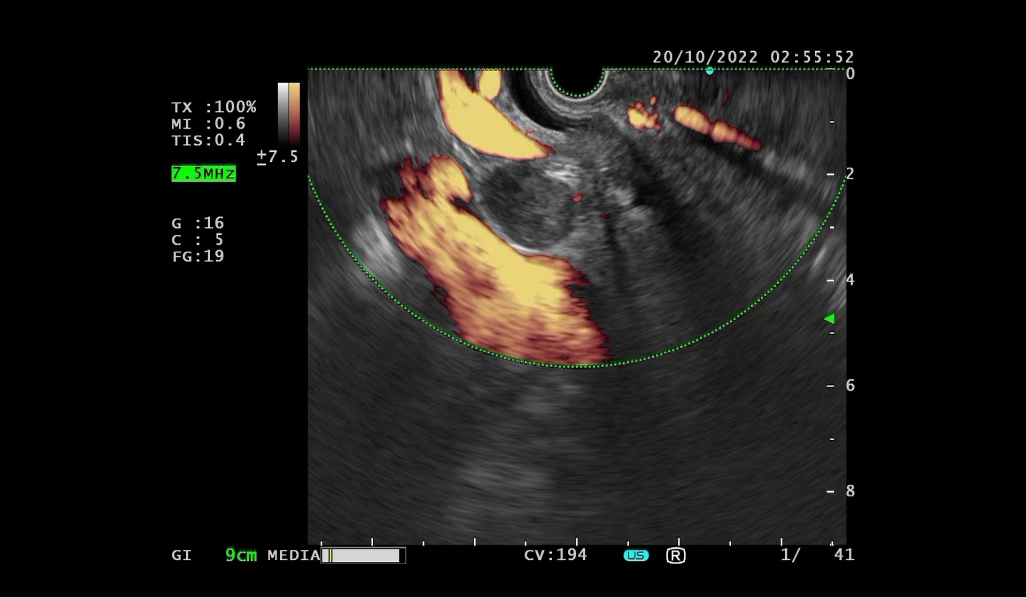

After admission, symptomatic treatments such as anti-infection therapy, enzyme inhibition, and fluid replacement were administered. Endoscopic retrograde cholangiopancreatography (ERCP) with nasobiliary drainage was performed. Endoscopic ultrasound revealed an irregular hypoechoic lesion in the pancreatic head, dilation of the main pancreatic duct, invasion of the pancreatic segment of the common bile duct, and a solid irregular lesion within the duct wall. An enlarged hypoechoic lymph node was observed near the portal vein. Pathological examination of the endoscopic ultrasound-guided pancreatic biopsy showed: (Pancreatic head puncture tissue) blood clot-like material with a small amount of pancreatic tissue, consistent with acute pancreatitis and necrotic changes.

Although the initial biopsy did not support a tumor diagnosis, abdominal MRI and endoscopic ultrasound suggested possible invasion of the common bile duct and enlarged lymph nodes near the portal vein. To avoid misdiagnosis, Spyglass examination was performed. Spyglass choledochoscopy revealed destruction, hyperplasia, and diffuse stenosis in the middle and lower segments of the bile duct, with fragile tissue prone to bleeding. Pathological examination confirmed adenocarcinoma of the distal common bile duct.